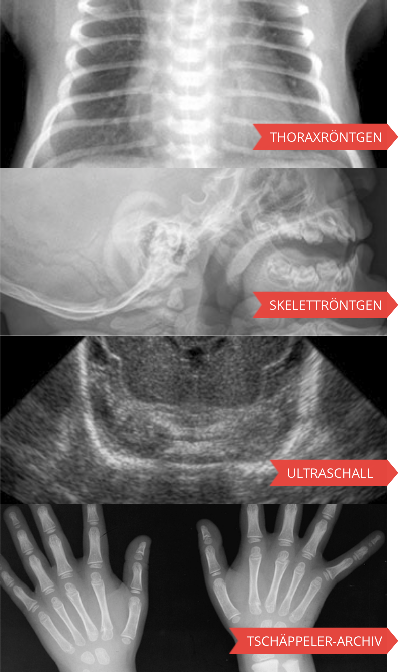

Berner E-Learning-Programme

Die wichtigsten Berner Lernprogramme können Sie direkt mit den links stehenden Verweisen aufrufen. Alle weiteren Lernprogramme finden Sie unter "zur Gesamtübersicht".